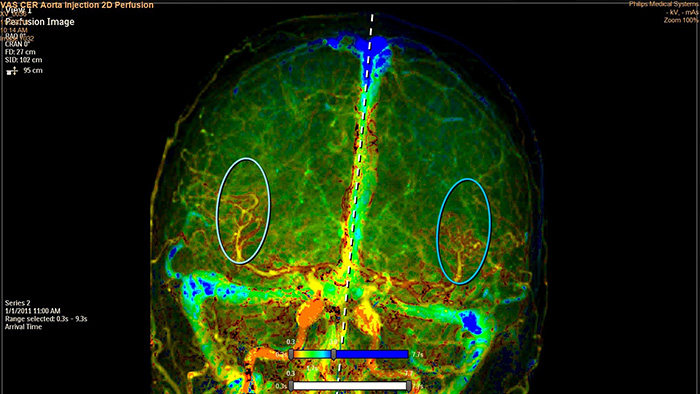

O SmartPerfusion é um software de análise de imagens que fornece informações funcionais sobre a perfusão do tecido com base em angiografia digital (DSA).